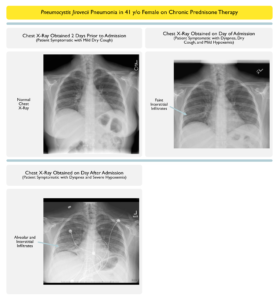

PJP CASE1A